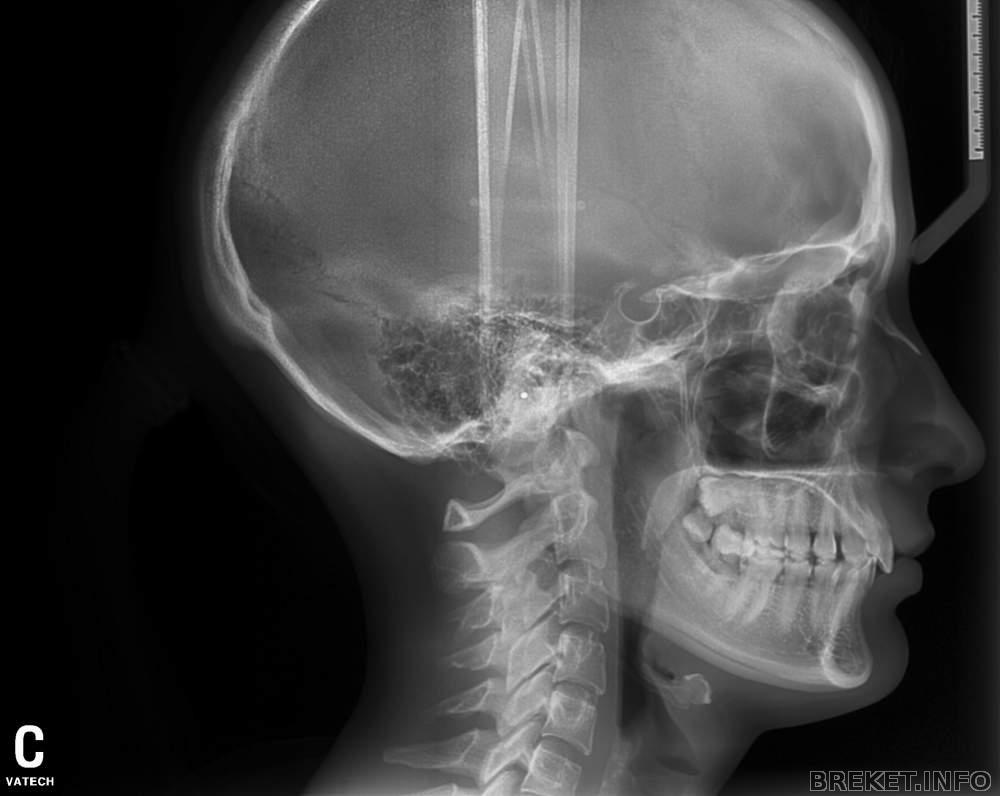

ТЕЛЕРЕНТГЕНОГРАММА (ТРГ) — Рентгеновский снимок черепа, выполненный по специальной методике. Отображает проецию костного скелета и мягких тканей черепа (губы, нос, щеки) в пропорциях близким к реальным. Может выполняться в прямой (анфас) или в боковой (в профиль) проекции. По ТРГ анализируется геометрия лица, выявляется характер и причина патологии, определяются допустимость и границы перемещений зубов, при этом оценивается изменение профиля лица пациента.